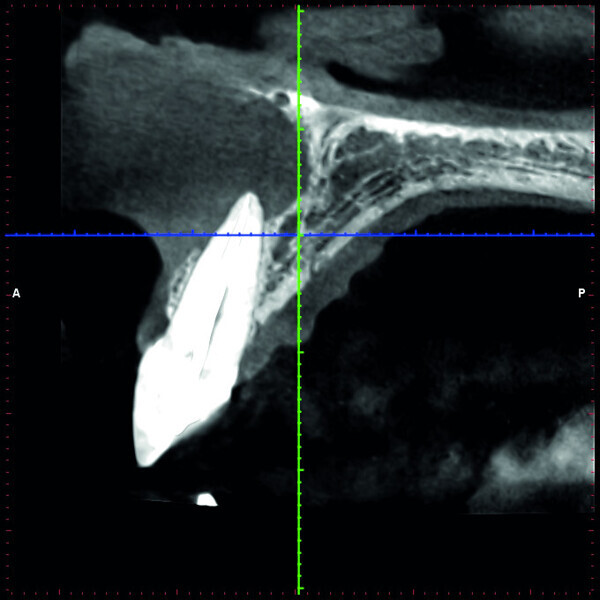

Fig. 2b: Conventional radiograph of an endodontically treated tooth #11 and cold-sensitive tooth #12 compared with CBCT imaging showing the presence of a large apical bone defect (taken at a two-day interval).